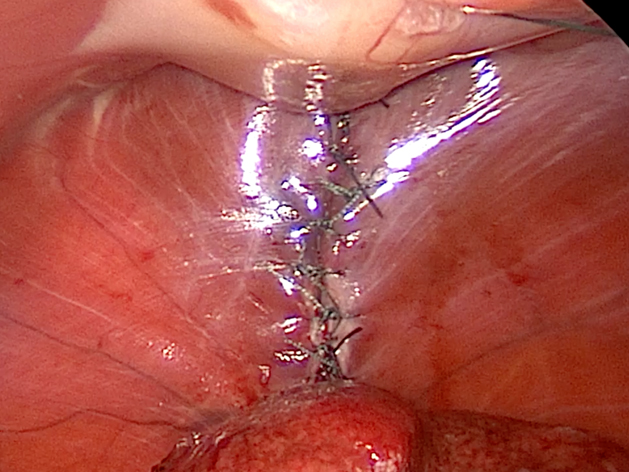

右:逸脱した臓器を戻した様子

横隔膜を整復した様子